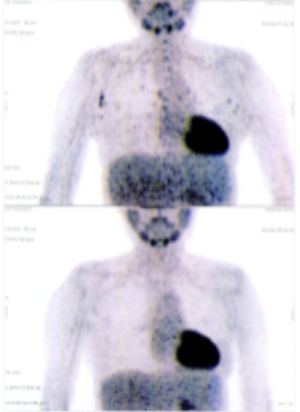

A 40+ woman with lung cancer and brain metastases failed all treatment including radiotherapy and chemotherapy. She cannot walk. After a few treatment, the left lung cancer is gone, and all the brain metastases are gone. She is starting to walk again. One set of pictures shows the left lung cancer, and the other set of pictures show the brain: on top is BEFORE TREATMENT, bottom is AFTER TREATMENT.

CASE NO: 31 AFTER TREATMENT

A 50+ year old female has recurrent Peripheral T-Cell Lymphoma that failed all treatment, and it has spread to lymph nodes in the axillary and mediastinal region, and to the lungs. The specialists gave her about 3 months to live. After just one treatment, the axillary/mediastinal nodes and the lung lesions are gone. One set of pictures shows the lymph nodes, and the other set of pictures show lung lesions. The picture on top is BEFORE TREATMENT, and the picture below is AFTER TREATMENT.

CASE NO: 34 AFTER TREATMENT